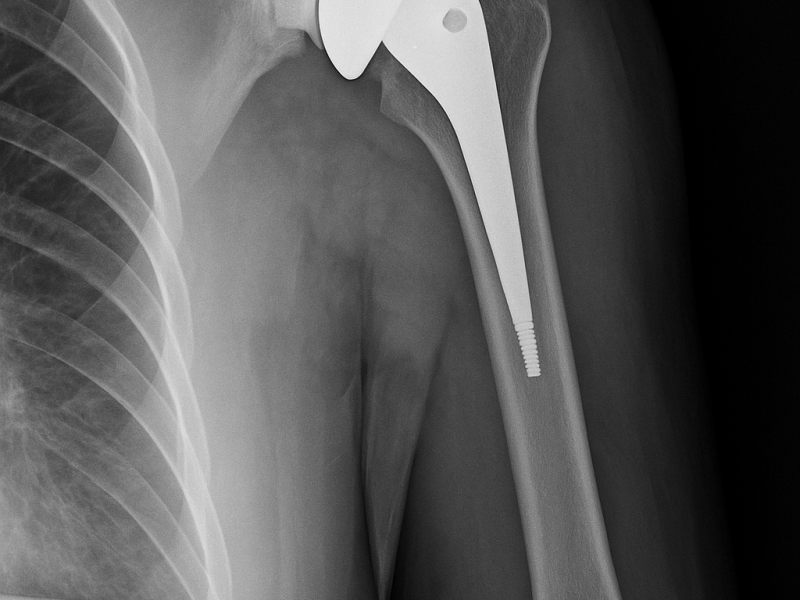

We provide advanced shoulder replacement surgery for patients suffering from arthritis, rotator cuff injuries, or severe joint damage, with the goal of restoring comfort and full range of motion.